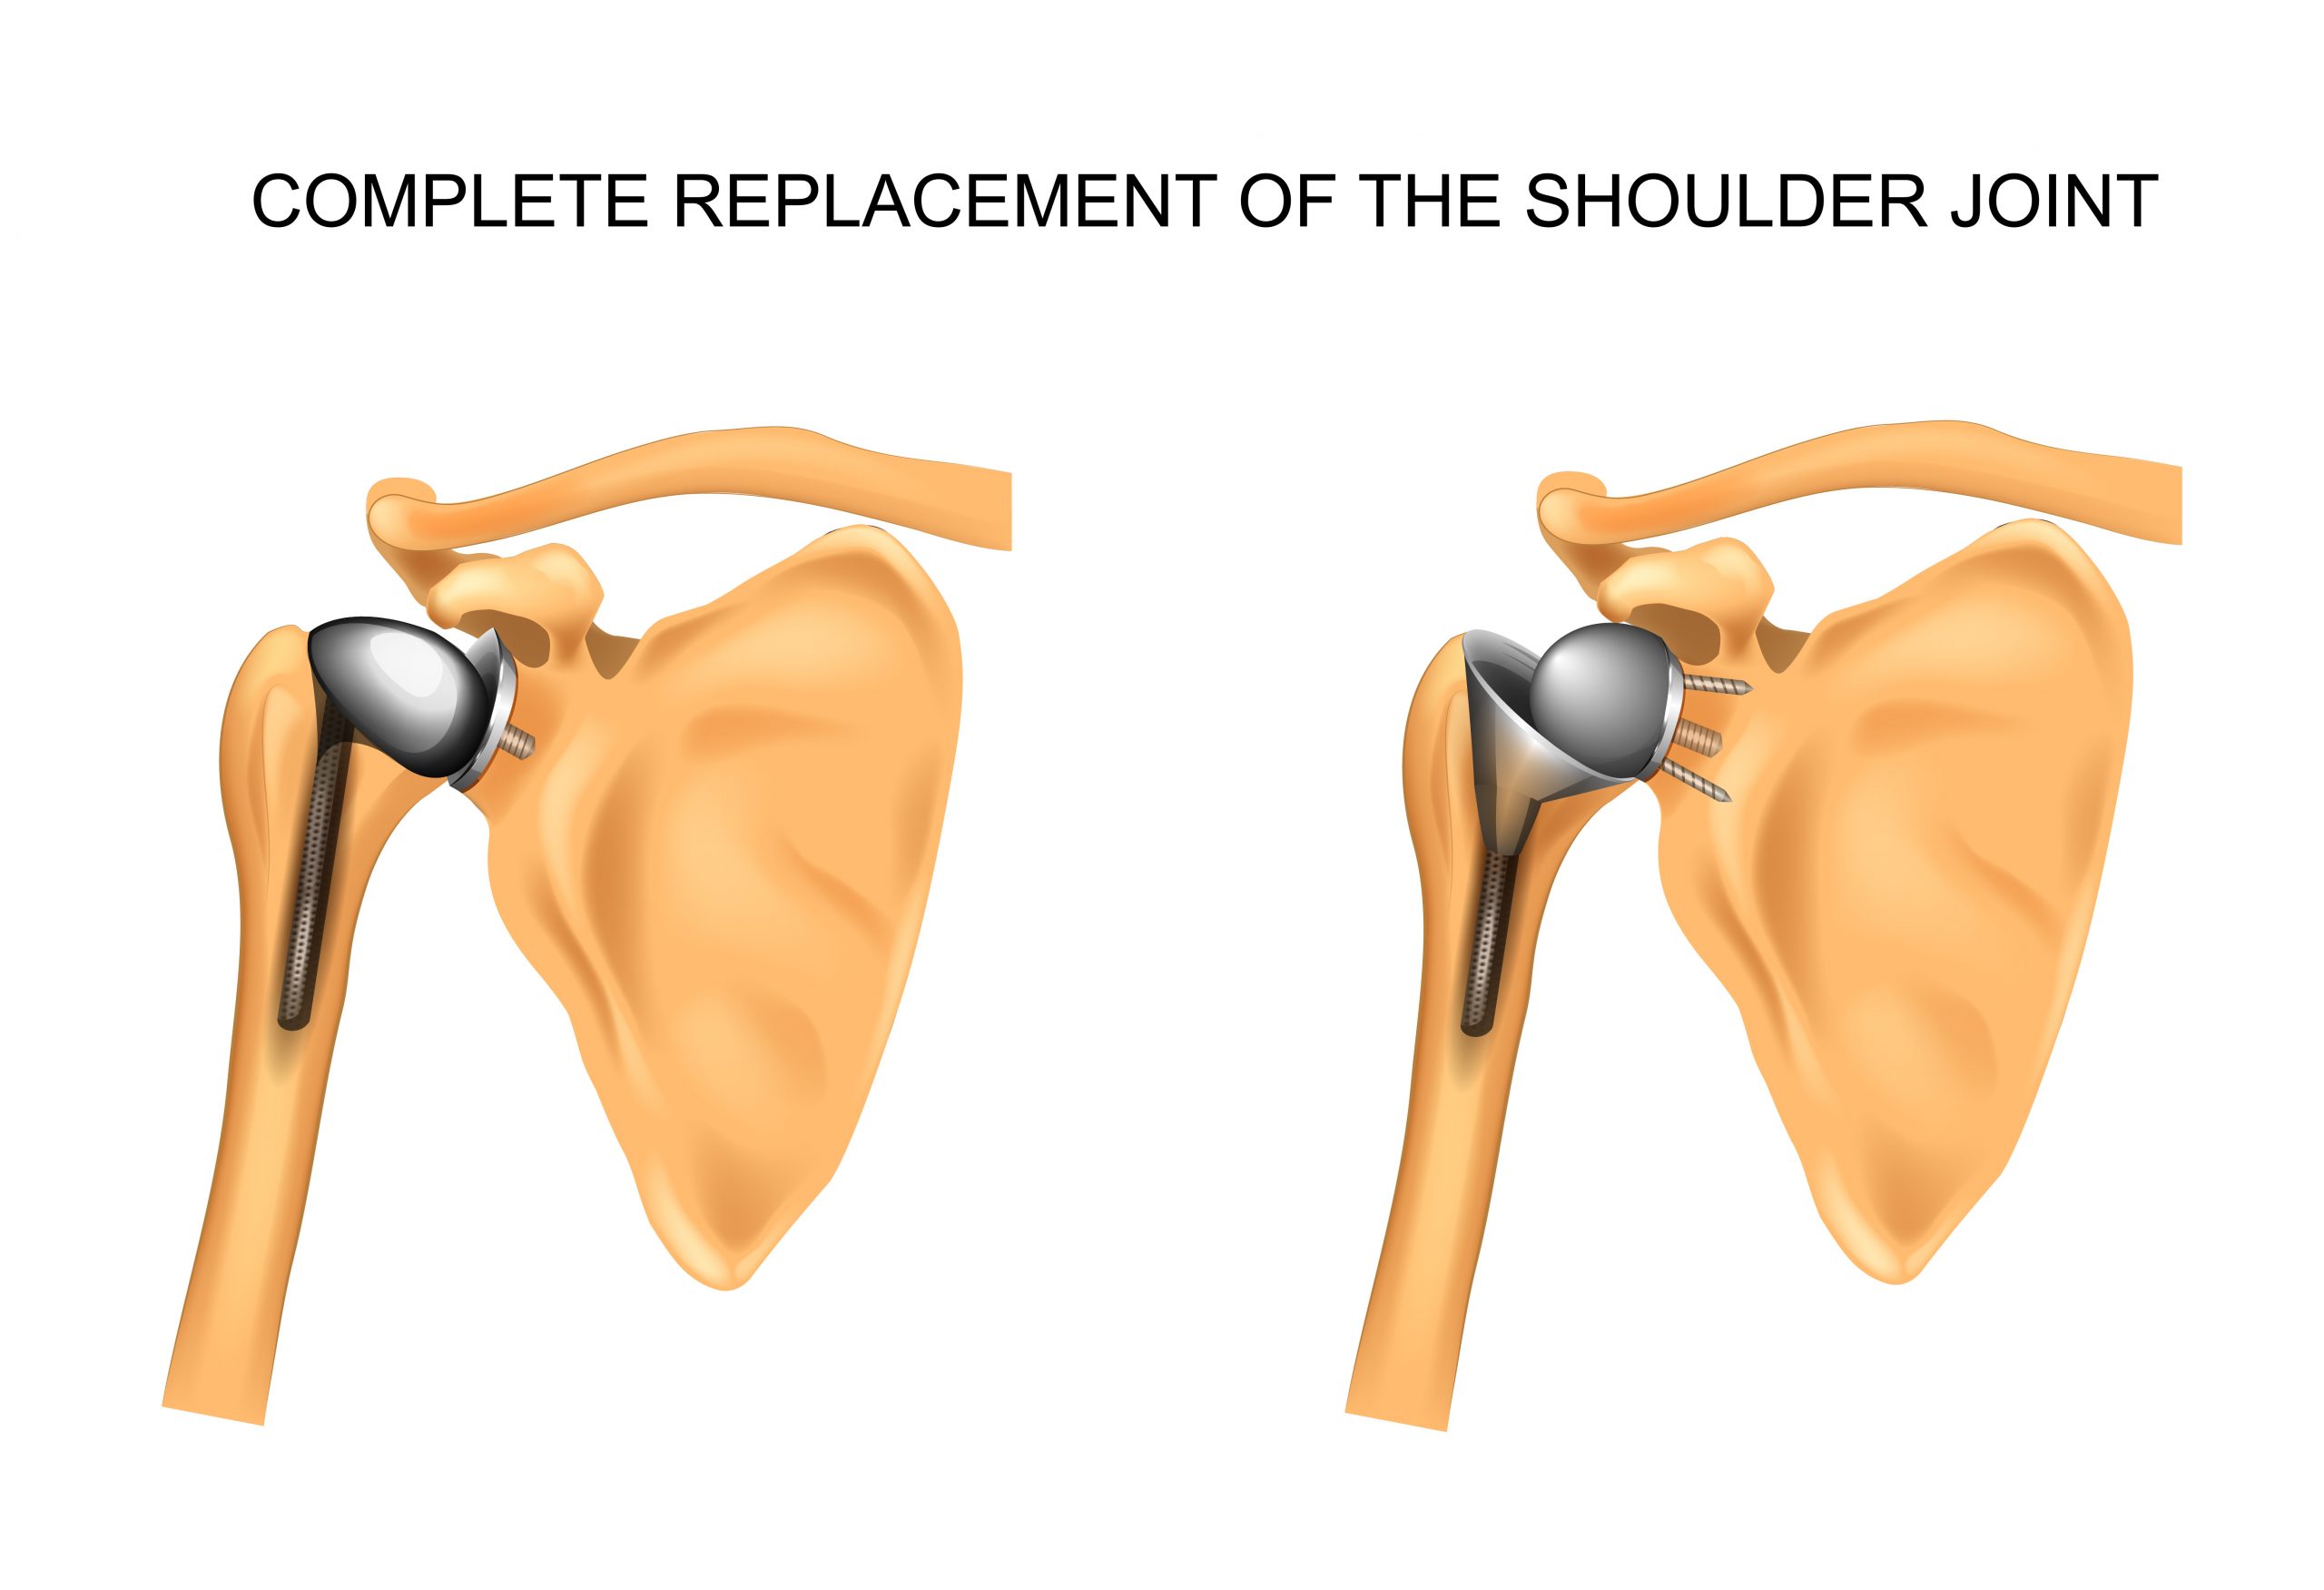

El hombro es una enartrosis lo cual quiere decir que el extremo redondo del hueso del brazo encaja dentro de la abertura en el extremo del omóplato. Este tipo de articulación permite mover el brazo en la mayoría de las direcciones.

Para el reemplazo total del hombro, el extremo redondo del hueso del brazo se reemplazará con una caña o vástago artificial que tiene una cabeza de metal redondeada. La parte de la cavidad (glenoide) del omóplato se reemplazará con una cubierta plástica y lisa (recubrimiento) que se sostendrá en el lugar con un cemento especial. Si sólo 1 de estos 2 huesos necesita ser reemplazado, la cirugía se denomina artroplastia parcial del hombro o hemiartroplastia.

Extraerá la cabeza (epífisis) del hueso de la parte superior del brazo (húmero).

Fijará con cemento la nueva cabeza y vástago de metal en el lugar.

Aplanará la superficie de la cavidad y fijará con cemento la nueva cubierta en el lugar.

El hombro es una enartrosis lo cual quiere decir que el extremo redondo del hueso del brazo encaja dentro de la abertura en el extremo del omóplato. Este tipo de articulación permite mover el brazo en la mayoría de las direcciones.

Para el reemplazo total del hombro, el extremo redondo del hueso del brazo se reemplazará con una caña o vástago artificial que tiene una cabeza de metal redondeada. La parte de la cavidad (glenoide) del omóplato se reemplazará con una cubierta plástica y lisa (recubrimiento) que se sostendrá en el lugar con un cemento especial. Si sólo 1 de estos 2 huesos necesita ser reemplazado, la cirugía se denomina artroplastia parcial del hombro o hemiartroplastia.

Extraerá la cabeza (epífisis) del hueso de la parte superior del brazo (húmero).

Fijará con cemento la nueva cabeza y vástago de metal en el lugar.

Aplanará la superficie de la cavidad y fijará con cemento la nueva cubierta en el lugar.